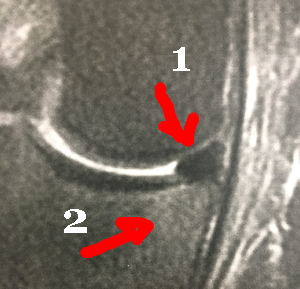

IRM de la Languette méniscale

Les signes sur l'IRM en faveur d'une lésion mécanique, sont la fissure verticale complète et l'amputation (1) de la pointe du triangle méniscal. Le bout du triangle est un morceau du ménisque, qui a migré : la languette.

La languette (1) est retrouvée ici sous le ménisque; elle repousse le ligament interne (3). L'os est un peu blanc (petit oedème osseux) (2) dans l'angle en regard de la languette, témoignant de l'inflammation locale.